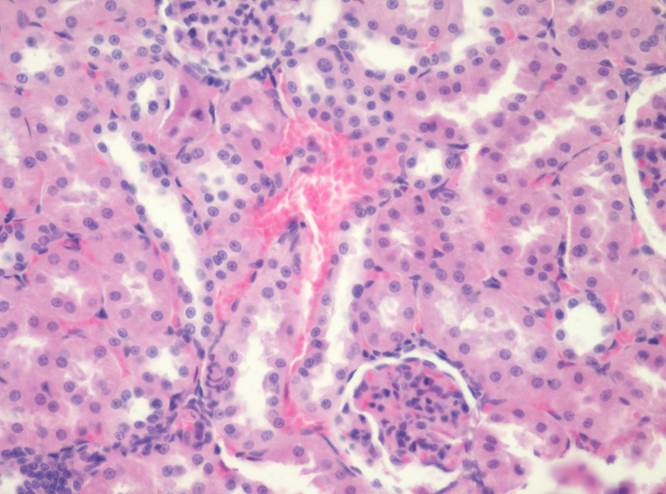

- Корковое вещество:

3. почечное тельце;

4. сосудистый клубочек;

5. наружный листок капсулы почечного тельца;

6. полость почечного тельца;

7. проксимальный извитой каналец;

8. дистальный извитой каналец.